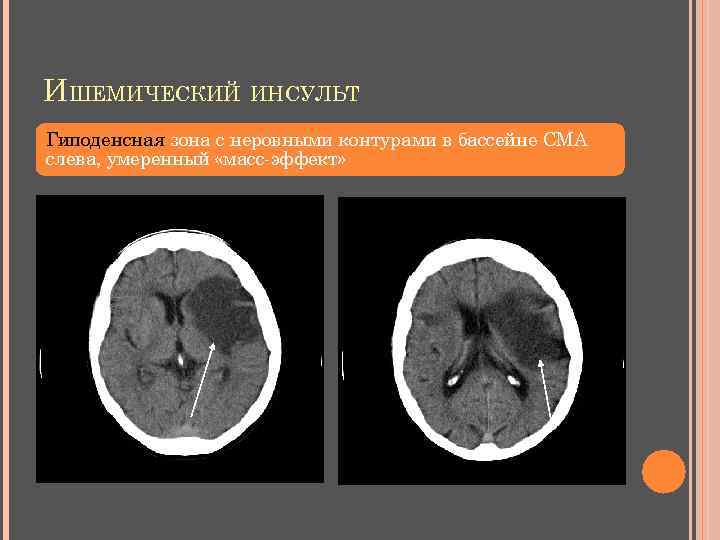

ИШЕМИЧЕСКИЙ ИНСУЛЬТ Гиподенсная зона с неровными контурами в бассейне СМА слева, умеренный «масс-эффект»